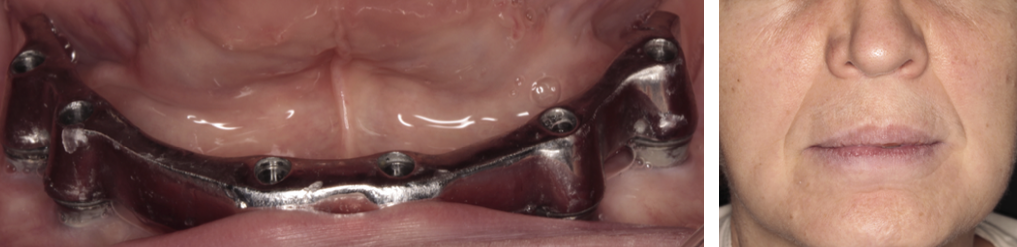

Mai întâi se realizează bara (Fig. 3.9.10) peste care se va aplica viitoarea lucrare. Apoi se realizează o machetă a lucrării pentru a analiza corectitudinea ocluziei (mușcăturii) (Fig. 3.9.11) precum și înălțimea dinților și aspectul facial al pacientului (Fig. 3.9.12, și Fig. 3.9.13).

Proteza stă pe bară fără să se miște deoarece în baza protezei există elemente de ancorare siliconate de culoare galbenă așezate aproape una de cealaltă pe toată suprafața bazei (Fig. 3.9.14). Acele elemente creează fricțiune între proteză și bară și nu permite desprinderea involuntară a acesteia, chiar dacă pacientul mestecă alimente lipicioase. Proteza poate fi îndepărtată cu mâna doar printr-o acțiune voluntară a pacientului. Acest tip de lucrare reface funcția masticatorie, pacienții bucurându-se de toate tipurile de alimente fără grija că proteza va cădea sau va sări.

Aspectul lucrării este unul natural, aceasta îmbunătățind estetica generală și fizionomia pacientului prin redarea conturului feței și plenitudinii obrajilor și a buzelor. Refacerea funcției masticatorii și redarea fizionomiei va aduce o îmbunătățire semnificativă a calității vieții pacienților care aleg acest tip de tratament (Fig. 3.9.15).